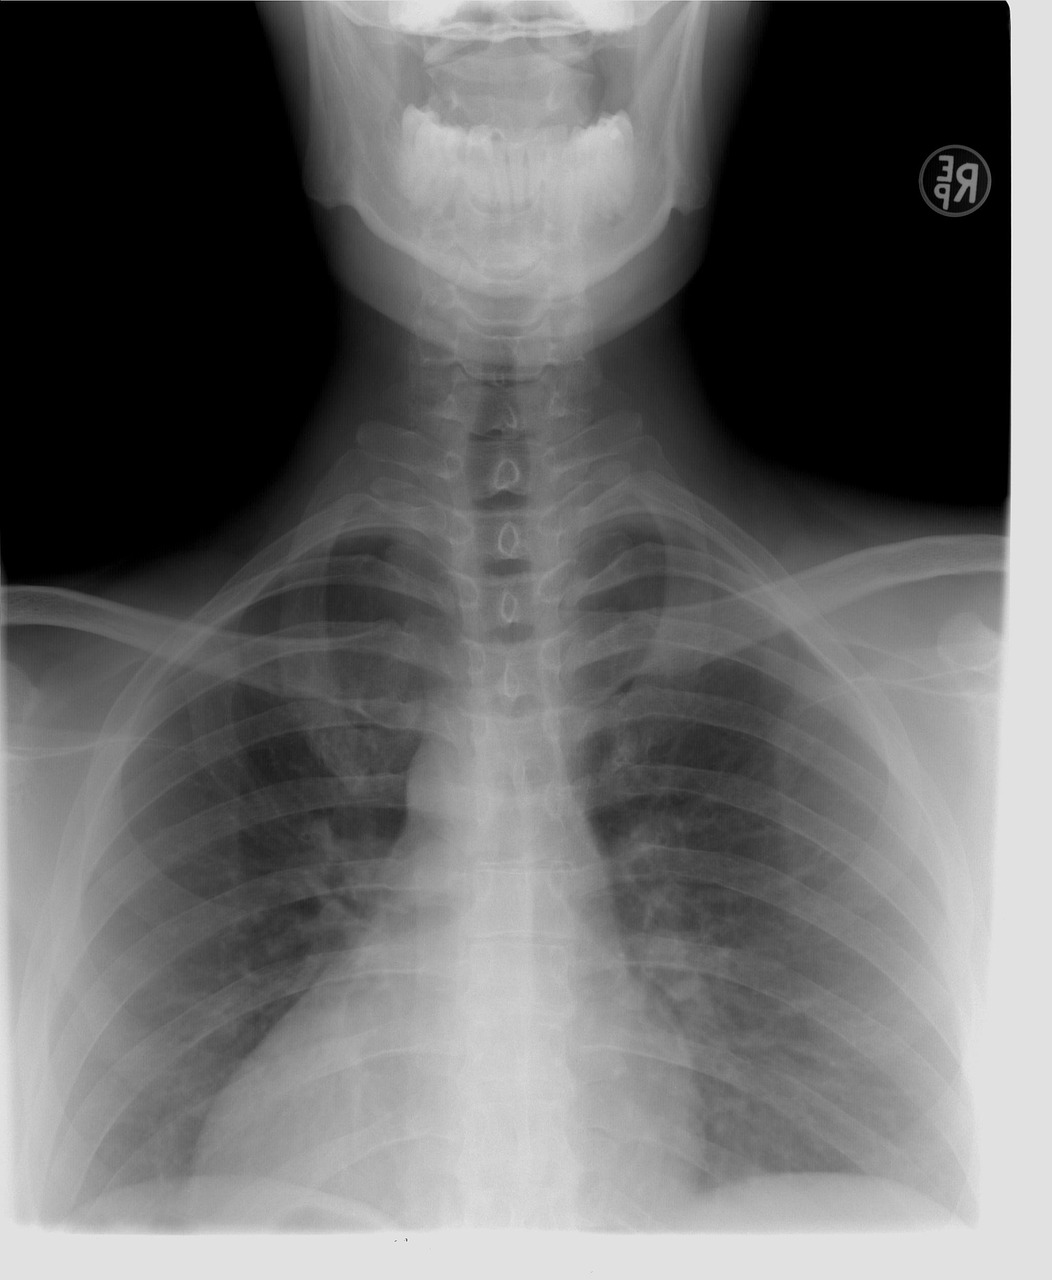

검진은 보통 키, 몸무게, 혈압, 시력, 청력 등 기본적인 신체 계측부터 시작됩니다. 이후 혈액 검사, 소변 검사, 흉부 X-ray 촬영, 심전도 검사 등 일반 건강검진 항목이 순서대로 진행됩니다. 암 검진 대상자의 경우, 추가적으로 위내시경, 대장내시경, 유방촬영술, 자궁경부암 검사, 간 초음파 등 해당되는 검사를 받게 됩니다. 위내시경이나 대장내시경 검사는 수면 내시경으로 진행될 수 있으며, 이 경우 검진 후 회복 시간이 필요합니다. 검진 중 궁금한 점이 있다면 언제든지 의료진에게 질문하고 안내에 따르는 것이 중요합니다. 모든 검사가 끝나면, 최종적으로 의료진의 안내를 받아 귀가합니다.

일반 건강검진은 대부분의 성인에게 기본적으로 제공되는 검진으로, 신체 계측, 혈액 검사, 소변 검사, 흉부 X-ray 등 기본적인 건강 상태를 파악하는 항목들로 구성됩니다.

- 흉부 X-ray 촬영 : 폐 결핵, 폐렴, 폐암 등 흉부 질환의 유무를 확인합니다.